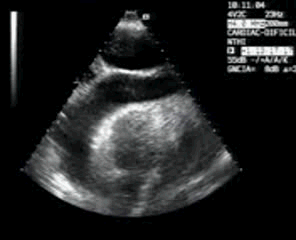

La segunda es la visualización de derrame pericárdico, que cuando es severo se observa en otros planos, pero que en caso de ser de menor cuantía, puede no ser visible en ningún otro abordaje (clip 17). No es el caso de este ejemplo, ya que se trata de un derrame pericárdico severo que produce un “swing-heart”, pero le tengo cariño a este clip por ser mi primera experiencia con los derrames.

The second is the visualization of pericardial effusion, which when severe is observed in other planes, but which, if it is of lesser quantity, may not be visible in any other approach (clip 17). It is not the case of this example, since it is a severe pericardial effusion that produces a «swing-heart», but I am fond of this clip because it is my first experience with spills.